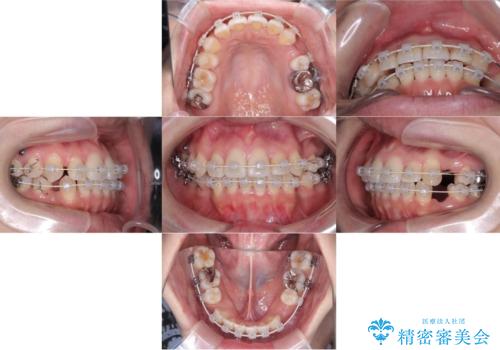

- 矯正装置

- ワイヤー

- 治療期間

- 3年

骨格的顎の変位を認めたため、顔貌に対しピッタリ上下の歯の正中を合わせることは難しいと説明し、上下左右計4本小臼歯を抜歯しワイヤー矯正治療を行いました。